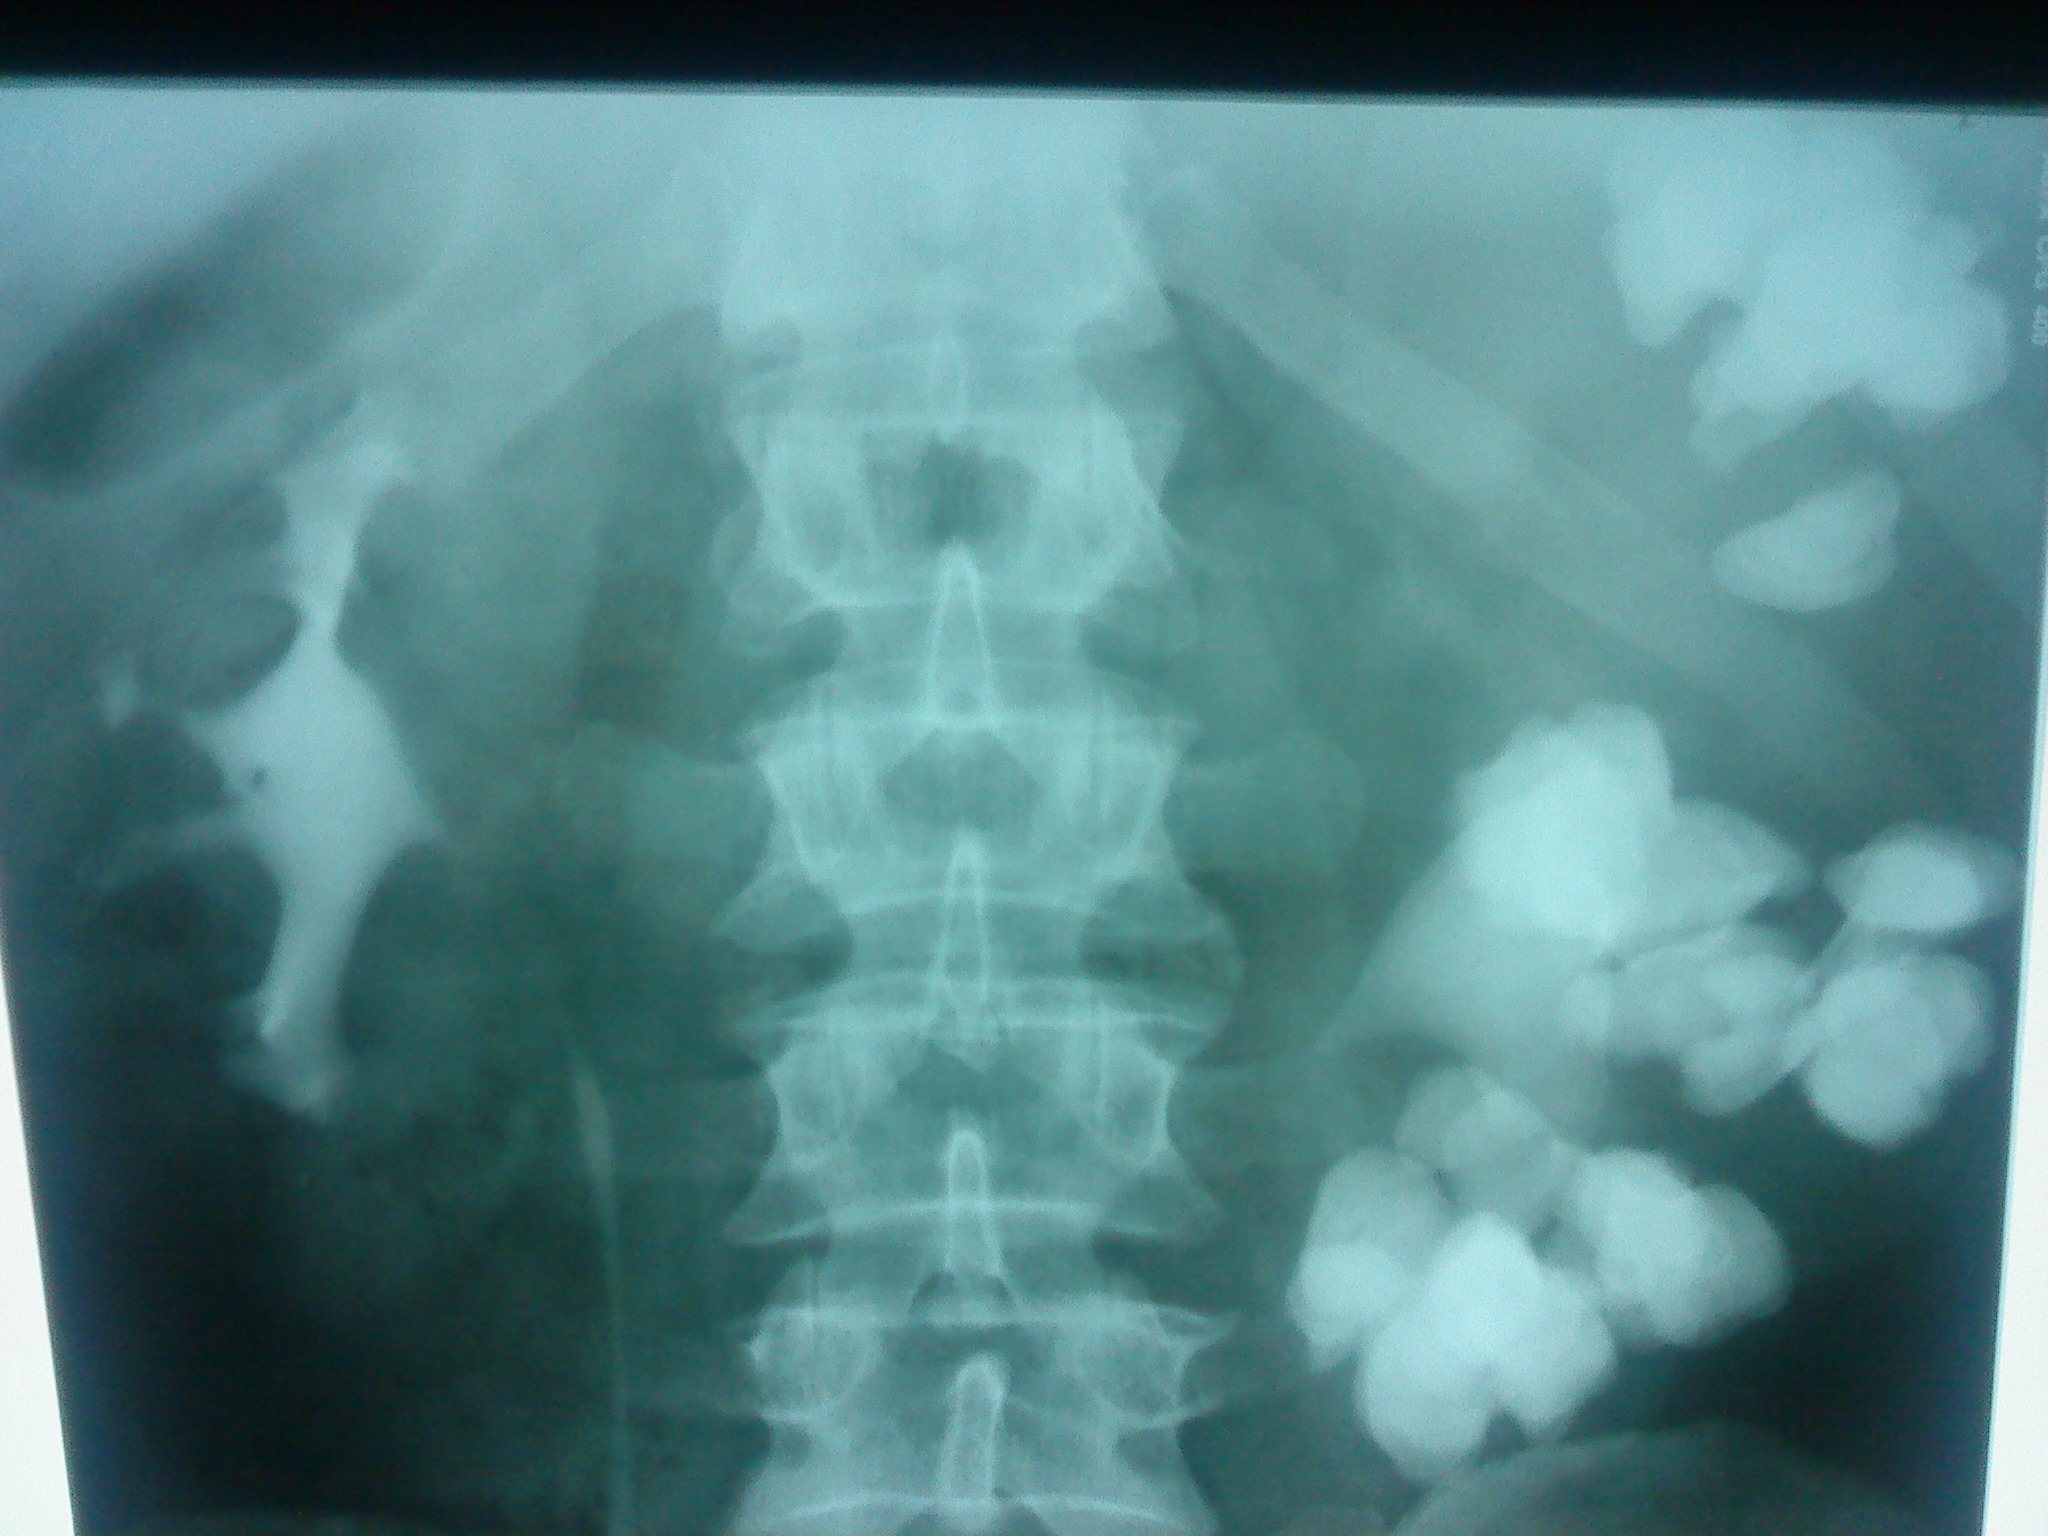

126. Урография

Просто интересный случай. Слева контрастирована только лоханка, остальное это тени конкрементов. К сожалению только один снимок.

Тип: Клиническое наблюдение

Область: Мочеполовая система

Модальность: Rg

Дата: 27.02.2013 - 18:32